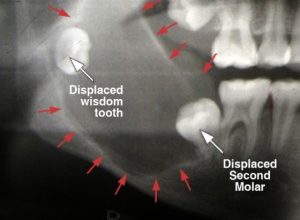

Jaw cysts, also known as dental cysts or maxillofacial

Jaw pain, also known as temporomandibular joint (TMJ)